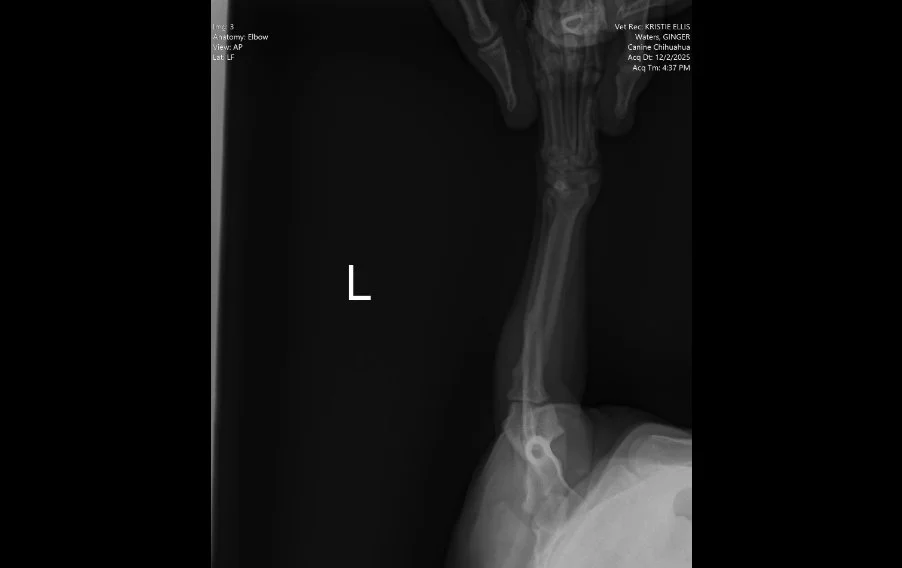

Image 3. Lateral radiograph of the left elbow and antebrachium.

Radiographs (Images 1–4) of the left forelimb, including the carpus, elbow, and shoulder identified:

• Mild degenerative joint disease (arthritis)

• Decreased shoulder joint space

• No fractures, masses, or bone lysis

Based on these findings, Ginger was treated for osteoarthritis. However, her clinical progression did not match the imaging results.

👉 This mismatch is critical. Radiographs are excellent for evaluating bone, but they cannot assess nerve roots, the spinal cord, or most soft tissue structures.